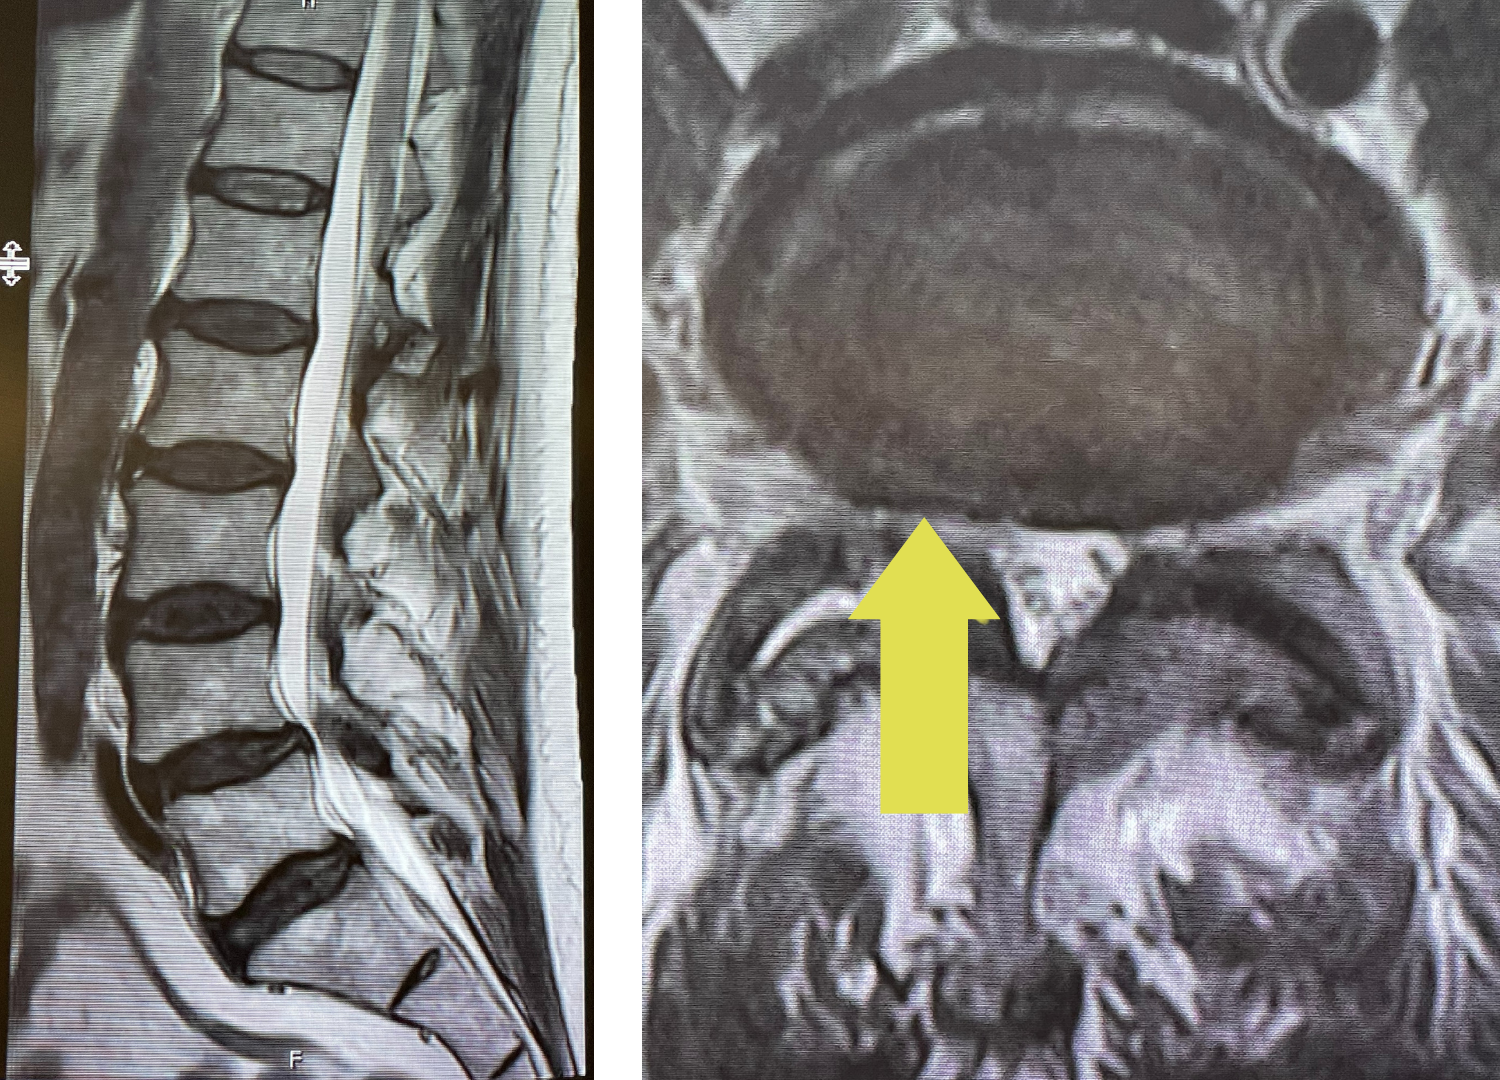

Figure 2. Illustration demonstrating an example of a lumbar In Situ fusion with bone graft material placed on top of transverse processes

At the time of surgery, it was noted that she had not only a very solid L4-S1 fusion but also her hardware was 100% encased in the bone. It was so much so that we decided not to remove this bone as we felt it would cause excess blood loss and perhaps add risk to neurological injury because of the force sometimes necessary to essentially “chisel” out this bone. We decided as a compromise, given her relatively young age and risk of redeveloping stenosis in the future, was to perform an “in situ” fusion from L2 to the top of the prior L4 fusion mass. It is to be remembered that the signal to form lumbar stenosis does not disappear once a laminectomy is performed, and a fusion prevents that signal. An “in situ” fusion is one where bone graft material is placed on the sides of the spine along bony extensions called transverse processes (Fig 2). The purpose of these processes besides serving as an excellent scaffold for bone graft material they also attach the back muscles or “paraspinal muscles” that allows a side or lateral bending motion or twisting. This way the patient will have reasonable stability after the bone consolidates and fuses. It has been found that a patient may not have to, with an in-situ fusion, have it be perfectly solid for it to serve the purpose of providing stability. The patient had an uneventful postoperative course.